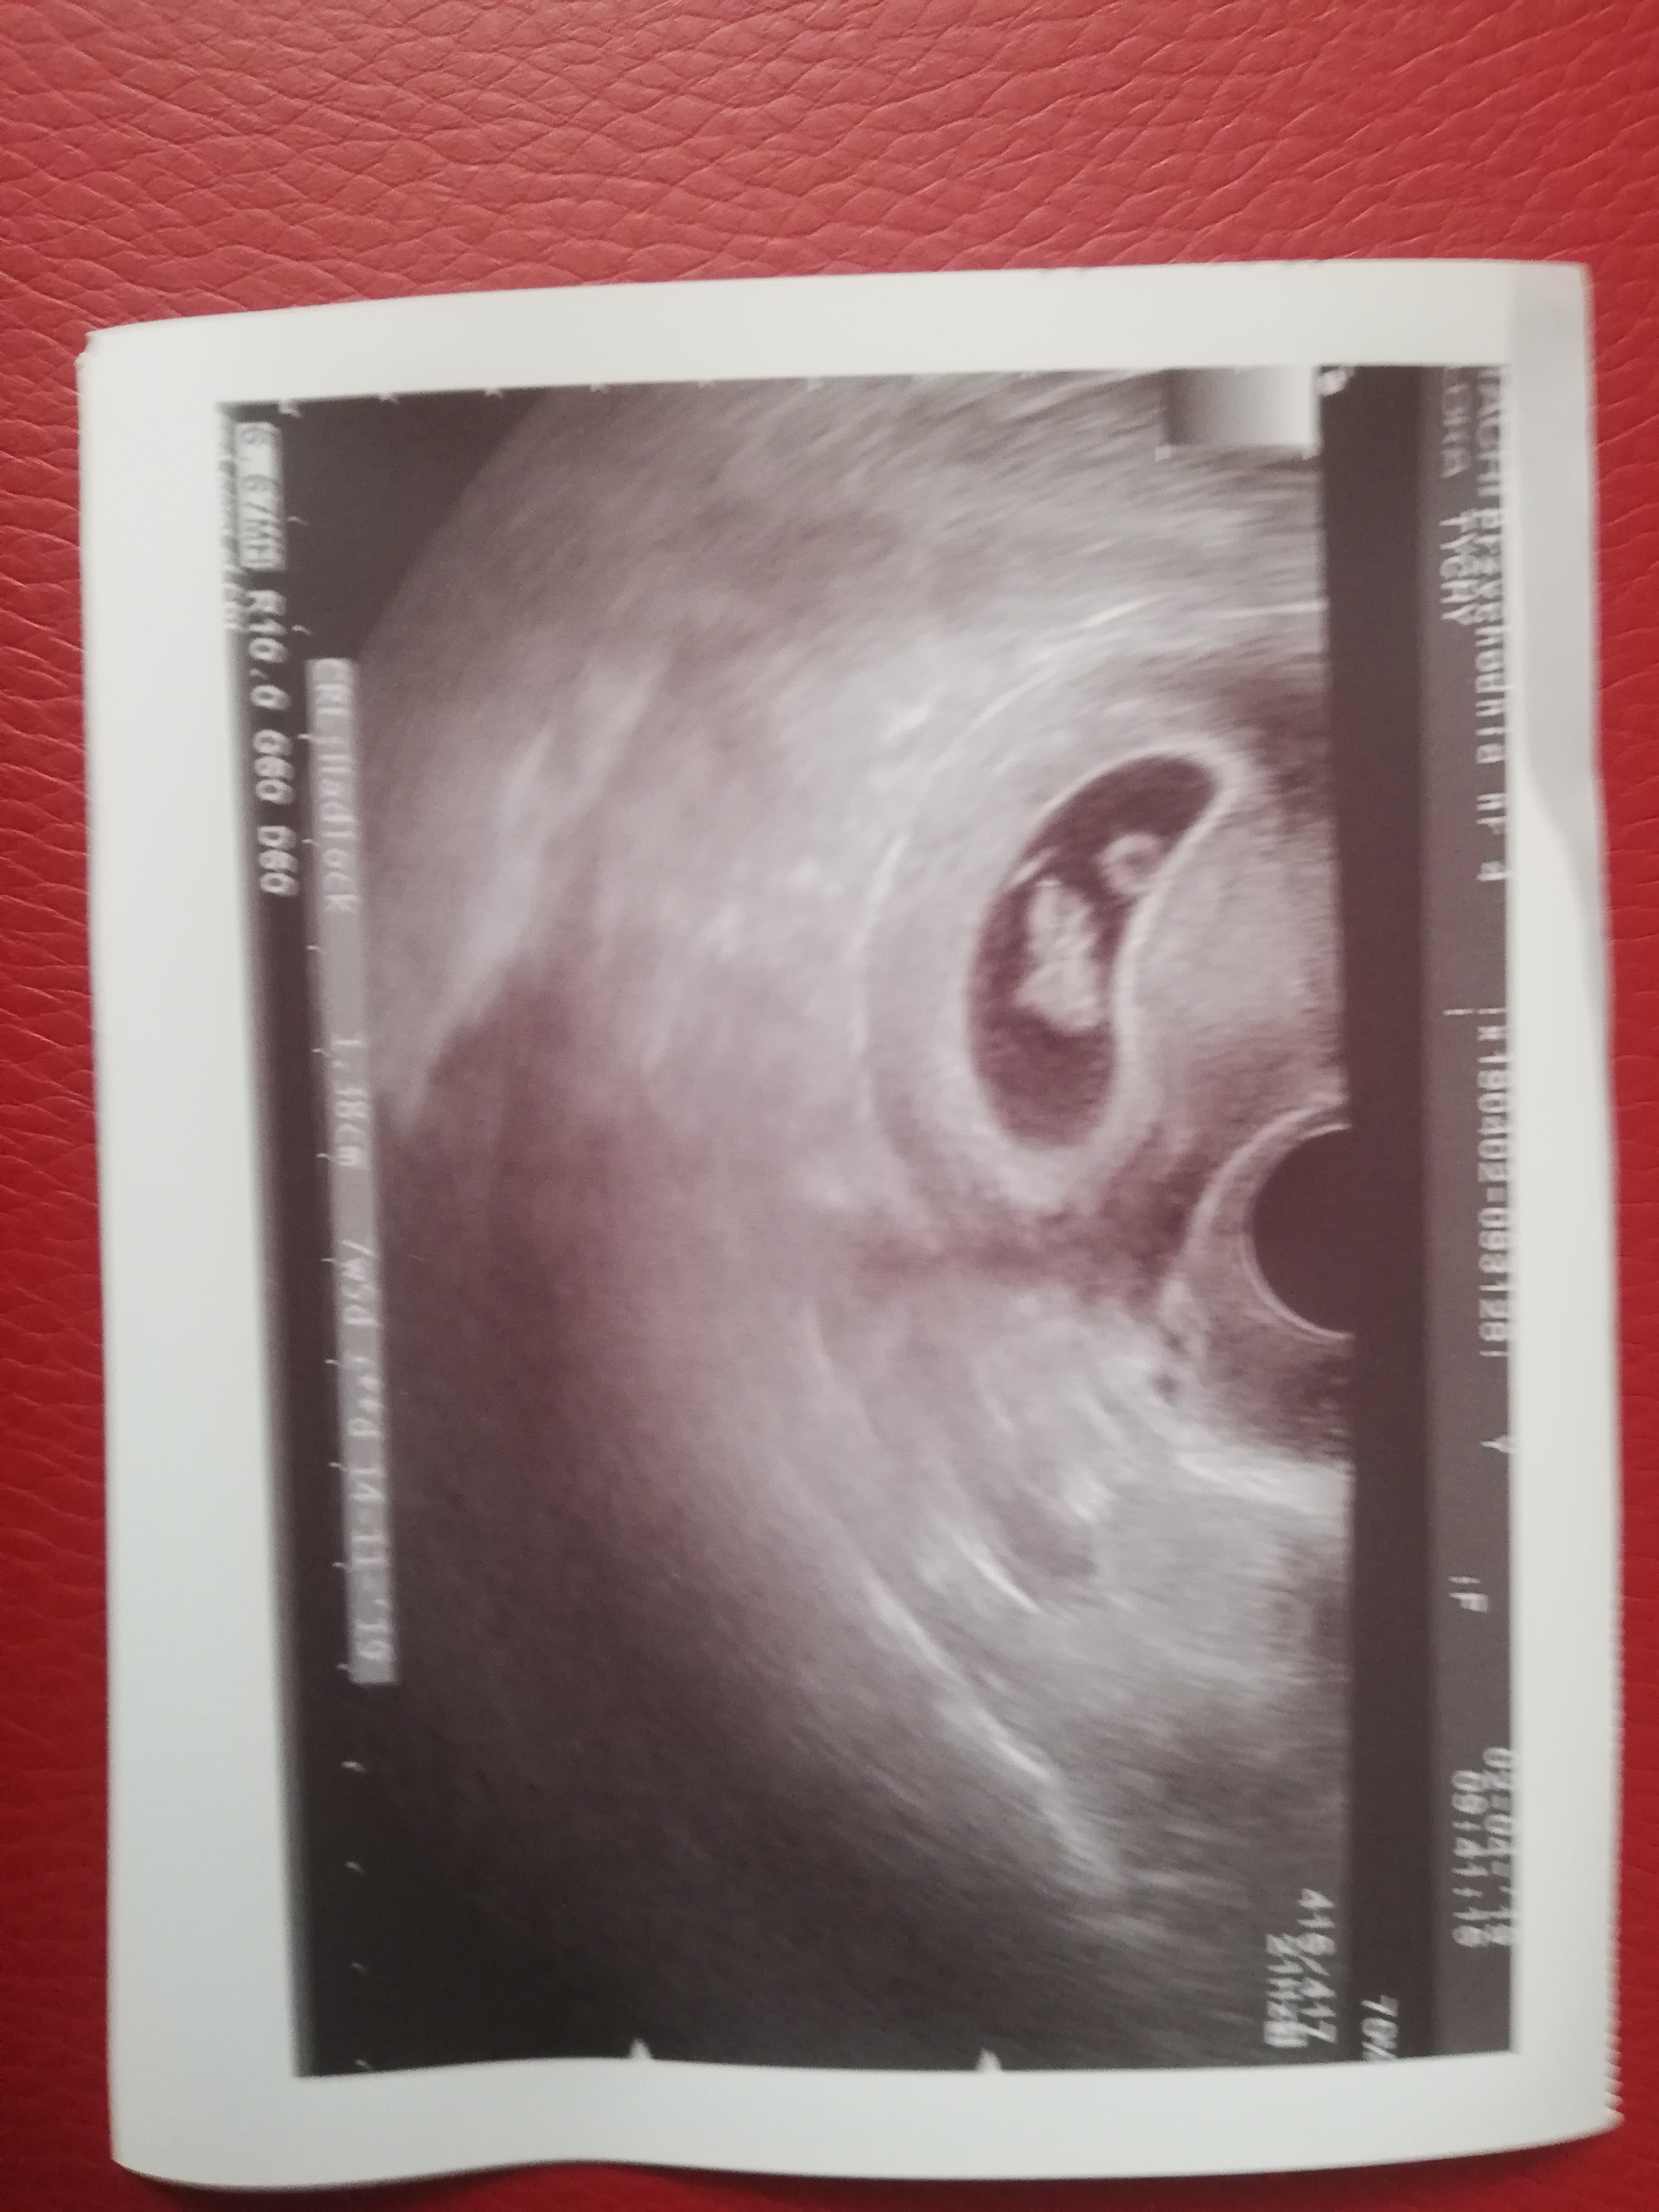

Byłam dziś u ginekologa, wyszło że jestem w ciąży.. Dał mi zdjęcie usg stwierdził że to 8 tydzień, gdy później się przyjrzalam zdjęciu czy one wyglądają jak bliźniaki? Ginekolog raczej by mi powiedział, choć to była moja pierwsza wizyta. Bardzo proszę o odpowiedź, to bliźniaki??

Wydaje mi się że to"stołówka" czyli ciałko żółte (coś takiego). Też miałam podobne zdjęcie usg w 8 tygodniu i myslalam że to bliźniaki gdyby to były bliźniaki lekarz na pewno poinformował by o takiej sytuacji